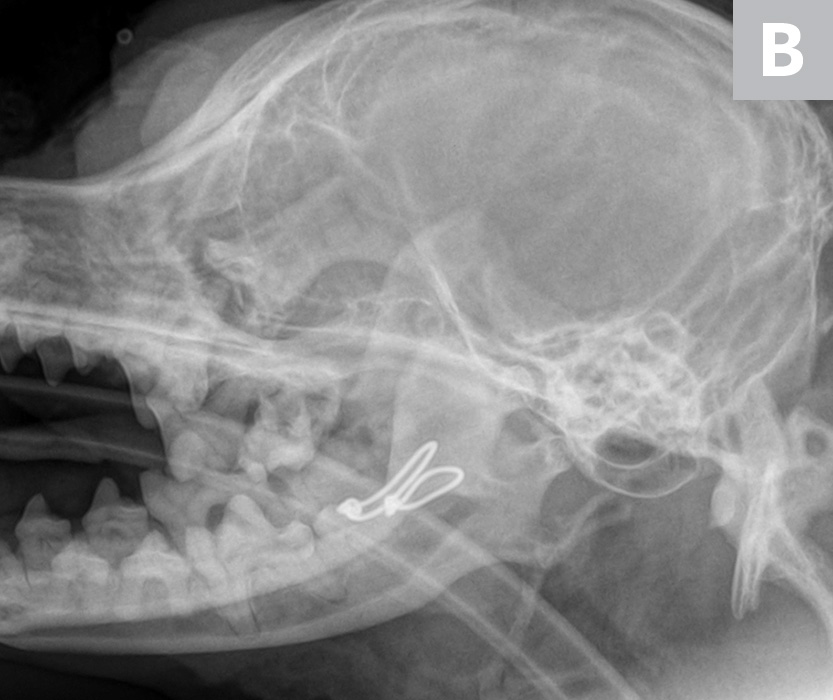

From www.cliniciansbrief.com

Jaw Fractures Clinician's Brief What Does A Fractured Jaw Bone Feel Like A broken jaw (or mandible fracture) is a common facial injury. What are the symptoms of a fractured jaw? A broken jaw (or mandibular fracture) is injury to the mandible, or jawbone. The appearance of a broken jaw can vary; A broken or dislocated jaw is an injury to the joint that connects your lower jawbone to the skull. A. What Does A Fractured Jaw Bone Feel Like.

Jaw Fractures Clinician's Brief What Does A Fractured Jaw Bone Feel Like A broken jaw (or mandible fracture) is a common facial injury. It’s a common type of facial fracture; Only the nose is broken more frequently. What does a broken jaw look like? It might show visible signs of swelling, bruising, or an abnormal jaw. A broken jaw (or mandibular fracture) is injury to the mandible, or jawbone. • pain, swelling. What Does A Fractured Jaw Bone Feel Like.